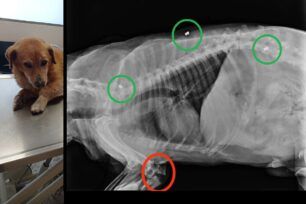

Στη Λάρσο στη Λέσβο ο ηλικιωμένος σκύλος που βλέπετε βρέθηκε στις 31 Δεκεμβρίου τραυματισμένος, χτυπημένος από όχημα με σπασμένη ουρά και πόδι. Οι ακτινογραφίες όμως έδειξαν και τα τρία μεταλλικά σφαιρίδια από αεροβόλο στο σώμα…διαβάστε περισσότερα

Στη Λάρσο στη Λέσβο ο ηλικιωμένος σκύλος που βλέπετε βρέθηκε στις 31 Δεκεμβρίου τραυματισμένος, χτυπημένος από όχημα με σπασμένη ουρά και πόδι. Οι ακτινογραφίες όμως έδειξαν και τα τρία μεταλλικά σφαιρίδια από αεροβόλο στο σώμα…διαβάστε περισσότερα